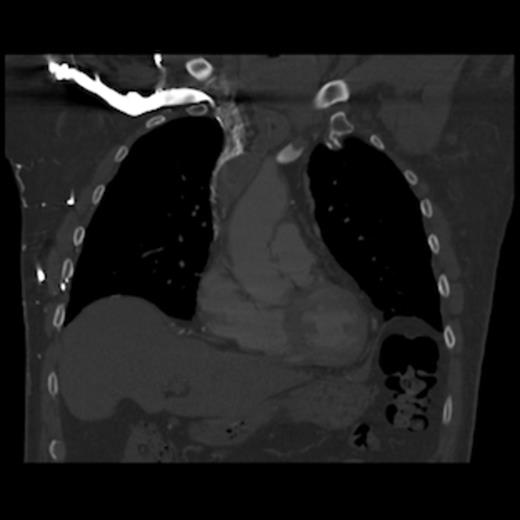

A 67-year old gentleman presented with progressive head and neck swelling and discomfort for several months. His symptoms were pronounced by bending over or straining in the bathroom. His symptoms worsened and he was referred for thoracic surgery consultation after a mass was seen on chest x-ray. He was diagnosed with SVC syndrome secondary to a mediastinal mass, demonstrated best by computed tomography (CT) [Figures 1, 2, 3].

CT of the chest (coronal section) with intravenous contrast: demonstrates complete obstruction of the superior vena cava by a large intramural thrombus that extends into brachiocephalic vein

CT of the chest (coronal section) with intravenous contrast: demonstrates large thrombus obstructing the superior vena cava down to the right atrium